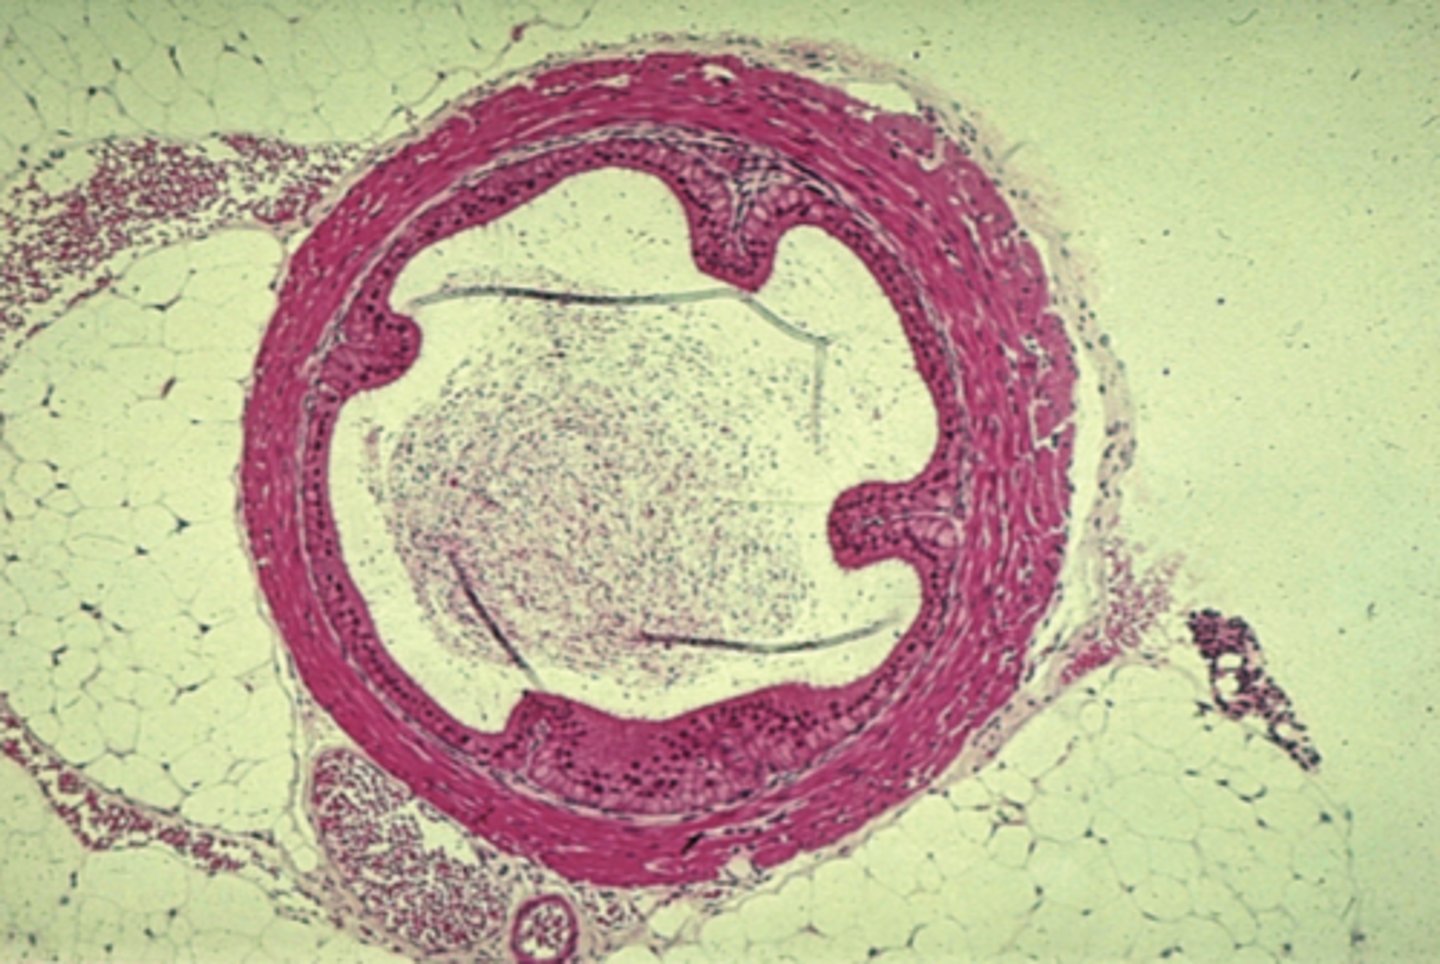

artery

what is this?

thicker inner wall

How to identify an artery